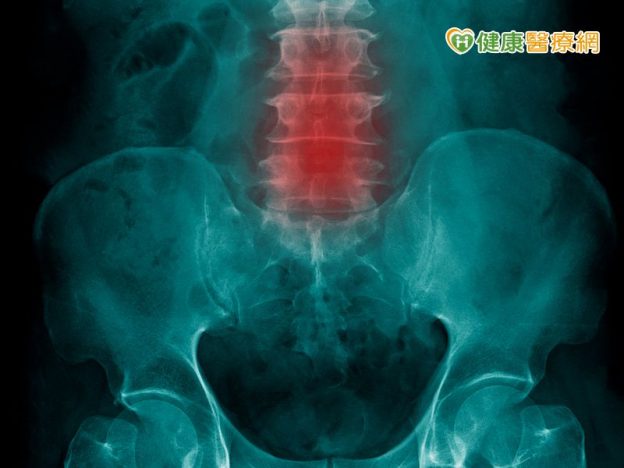

很多人都有下背痛的困擾,至於下背痛的成因不少,有人是因為肌腱發炎,也有人是因為腰椎關節退化導致;醫師指出,若確診為腰椎關節退化,可以用高頻熱凝神經阻斷術來改善疼痛,除非病況嚴重才需要手術治療;所以,若是有相關疾病,千萬別隱忍疼痛,反而使心裡鬱卒!

神經阻斷術是一種高頻熱凝治療,張鵬遠醫師指出,此方法是用一根長約15-20公分細針,在X光或超音波下定位進入腰部疼痛的部位,以特定波長與頻率和溫度做燒灼神經阻斷術,根據不同神經纖維,溫度可分為攝氏40至80度,攝氏80度會針對神經節部位,且燒灼的是感覺神經而不是運動神經。

進行神經阻斷術一次大約10-30分鐘,治療一次就可有明顯的效果;張鵬遠醫師解釋,下背痛原因很多,如果是腰部關節退化,大約以神經阻斷術治療一次就可改善,改善後有效期大約4至6個月會不痛,但是可能又會再復發。如果腰椎關節退化程度還不用開刀,就適合做,雖然此方法有侵入性,但並不是手術。